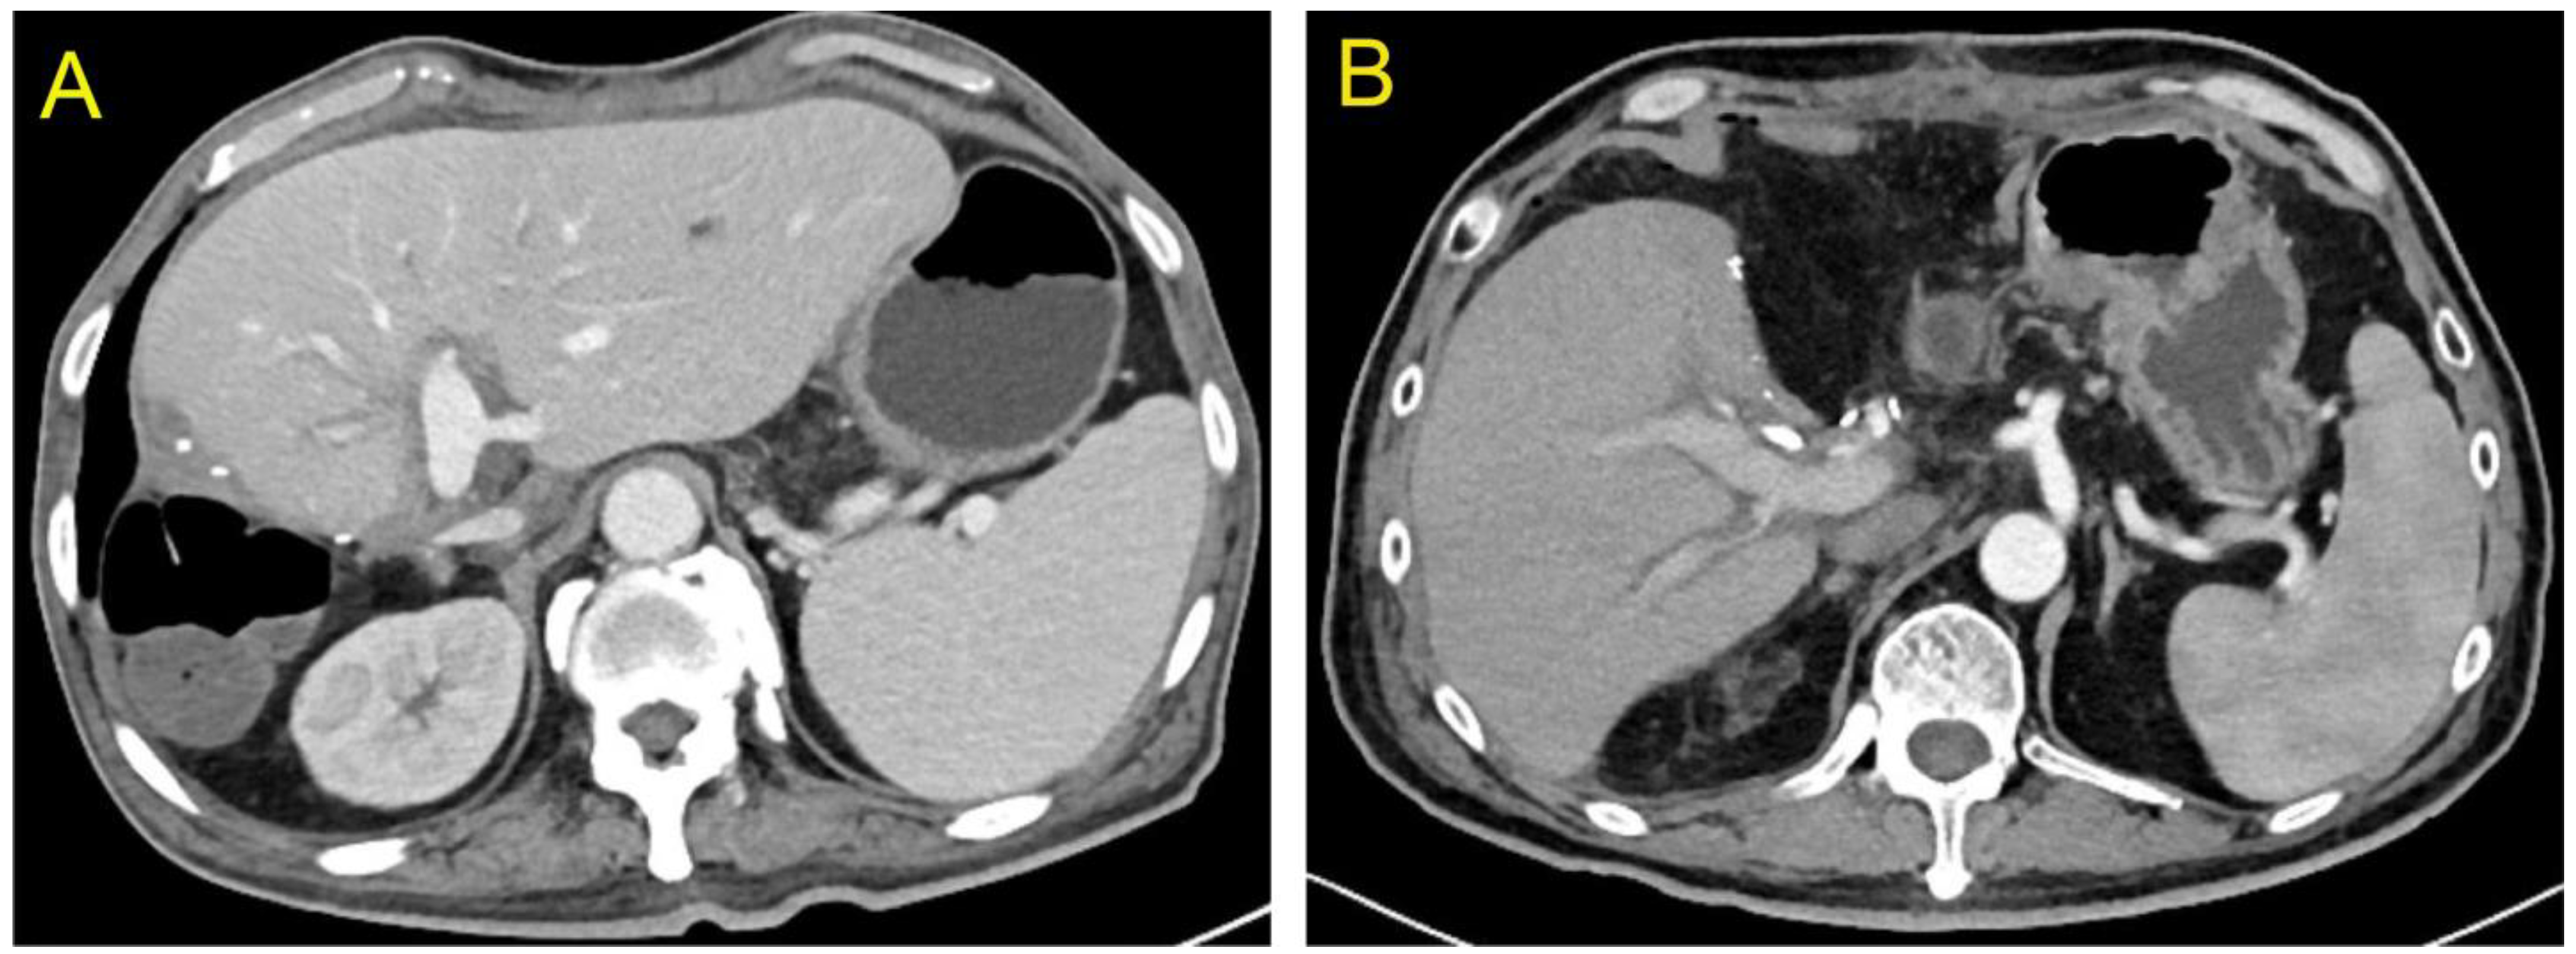

2.3. Recipient Characteristics

3. Results